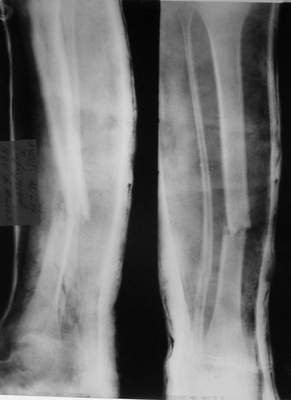

Re: псевдоартроз

A> Так как речь зашла непосредственно о травме, см этапные

A> снимки. Как все было

Вопросов нет.

Встречаются и при переломах голени (б/б с вальгусным смещением).

A> Тем более с такой дугой

См. аттачт.

A> и на этом

A> уровне.